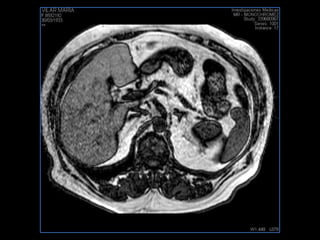

PROTOCOLO hígado graso AXIAL in phase y out phase AX T1 y AX fat sat +SAG T2  CON   GADOLINIO :  COR T1+AX T1(DIN) SAT: NO  FASE: RL THK: 4MM  COIL:  GAP: (FACTOR 1.4)  FOV: 40 CM NEX:2 SINCRONIZACION RESPIRATORIA EN 3 O 4 CICLOS ALE

PROTOCOLO hemocromatosis AXIAL supresión grasa /AX multieco en higado COR T2 AX T1 +SAG T2  CON   GADOLINIO :  COR T1+AX T1 SAT: NO  FASE: RL THK: 4MM  COIL:  GAP: (FACTOR 1.4) 1MM FOV: 40 CM NEX:2 SINCRONIZACION RESPIRATORIA EN 3 O 4 CICLOS ALE